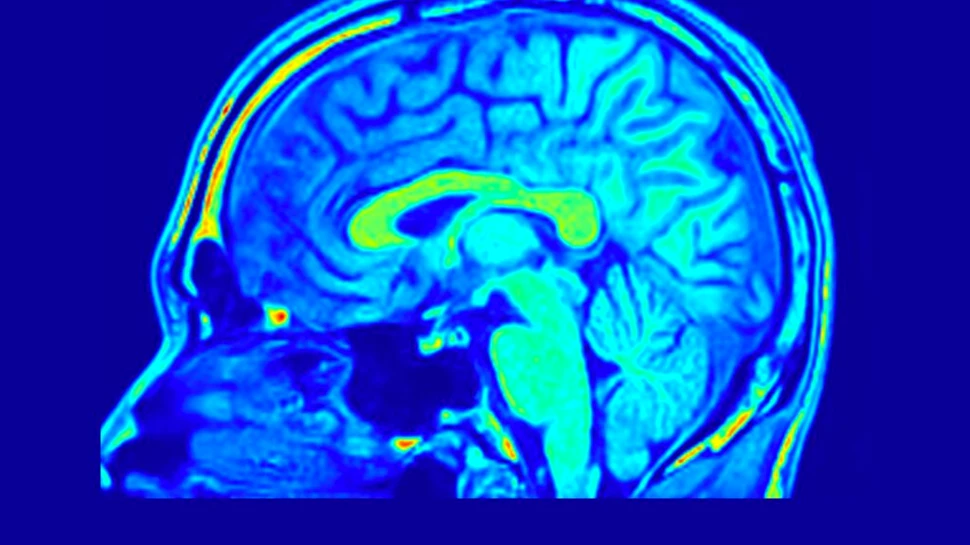

O iluzie apare atunci când vedem și percepem un obiect care nu corespunde cu stimulul senzorial ce ajunge la ochii noștri.

Într-un nou studiu publicat în Nature Neuroscience, cercetătorii de la University of California, Berkeley, în colaborare cu echipe de la Allen Institute, au identificat circuitul neuronal cheie și tipul de celule care joacă un rol central în detectarea acestor iluzii – mai exact, a marginilor sau „contururilor” lor – și modul în care funcționează acest circuit.

Hyeyoung Shin, Ph.D. (în prezent la Seoul University), Hillel Adesnik, Ph.D., și echipa lor au descoperit un grup special de celule numite neuroni IC-encoder, care „spun” creierului să vadă lucruri care nu există cu adevărat, ca parte a unui proces numit completare recurentă a tiparelor.

Acești neuroni primesc semnale de sus în jos din ariile vizuale superioare. Reprezentarea iluziei apare mai întâi în aceste arii și apoi este transmisă înapoi către cortexul vizual primar, unde este preluată de IC-encoders.

Pentru a demonstra mecanismul, cercetătorii au observat activitatea electrică a creierului la șoareci expuși la imagini iluzorii.

Apoi au folosit o tehnică numită optogenetică holografică cu doi fotoni, pentru a stimula neuronii IC-encoder chiar și în absența unei iluzii. Rezultatul: aceștia au reprodus aceleași tipare de activitate cerebrală întâlnite când imaginea iluzorie era prezentă, scrie MedicalXpress.

Descoperirea aruncă lumină asupra modului în care sistemul vizual și percepția funcționează în creier și are implicații pentru bolile în care acest sistem dă erori, cum este schizofrenia.

Concluzia studiului schimbă paradigma: viziunea și percepția nu sunt un proces pasiv, în care doar „primim” informații din jur, ci un proces activ, în care creierul construiește și interpretează realitatea prin calcule complexe.

Cu alte cuvinte, vederea noastră este mai puțin ca o cameră foto care redă fidel lumea și mai mult ca un monitor de computer, care afișează o imagine creată pe baza experiențelor și interpretărilor anterioare.